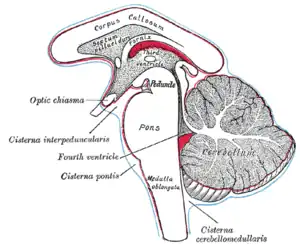

Duret haemorrhages are small linear areas of bleeding in the midbrain and upper pons of the brainstem. They are caused by a traumatic downward displacement of the brainstem.[1]

Duret haemorrhages are named after Henri Duret,[3] who discovered these brainstem lesions in dogs with increased intracranial pressure.[4] They are small linear areas of bleeding in the midbrain and upper pons of the brainstem.

They are caused by a traumatic downward displacement of the brainstem with parahippocampal gyrus herniation through the tentorial notch.[5] or acute hematoma, edema following trauma, abscess, or tumor.

Duret haemorrhages are haemorrhages secondary to raised intracranial pressure with formation of a transtentorial pressure cone involving the front part of the cerebral peduncles, the cerebral crura. Increased pressure above the tentorium may also involve other midbrain structures.

Kernohan's notch is a groove in the cerebral peduncle which may be caused by this displacement of the brainstem against the tentorial incisure. The resulting ipsilateral hemiparesis is a false localising sign,[6] known as the Kernohan-Woltman syndrome.[7] This may succeed or accompany temporal lobe (uncal) herniation and subfalcian herniation secondary to a supratentorial mass.

The pathophysiological mechanism is uncertain[8] but is probably caused by the displacement of the brainstem stretching and tearing perforating branches of the basilar artery to the pons; venous infarction may play a role.